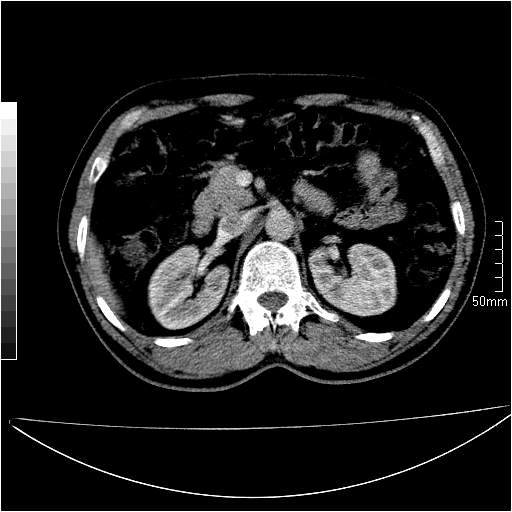

男性,54岁,皮肤黄染,搔痒一周余.b超示肝左叶回声异常.初步诊断1胆总管下段结石2胆囊结石伴慢性胆囊炎请各位战友帮忙看一下肝脏多发低密度如何解释恰当.增强效果不是很好.请大家见谅.

首先,胆总管下端结石梗阻伴肝内胆管扩张可确定。

其次,增强动脉期肝静脉显影,肝实质密度不均。——此为右心功能不全引起肝淤血的表现。

另外,肝八段低密度占位,呈多灶性,考虑肝脓肿或肝癌可能,(图像质量欠佳)建议进一步检查。

既然做了增强,为什么光提供延时期片子,肝动静脉期肝右叶前下段病灶增强如何?另外胆囊壁增厚,欠规整,内密度不均,与肝右叶病灶分界不清,增强表现怎样?肝内胆管轻度扩张,胆总管扩张,但未见明显结石影,也应提供增强早期图像才好鉴别扩张原因。片子较清,但不够完整,暂考虑1.胆囊癌肝局部浸润,或肝癌胆囊侵犯,2.胆总管下端或胰头钩突部占位。总之本人看不明白,请高手画图指示,先谢了!